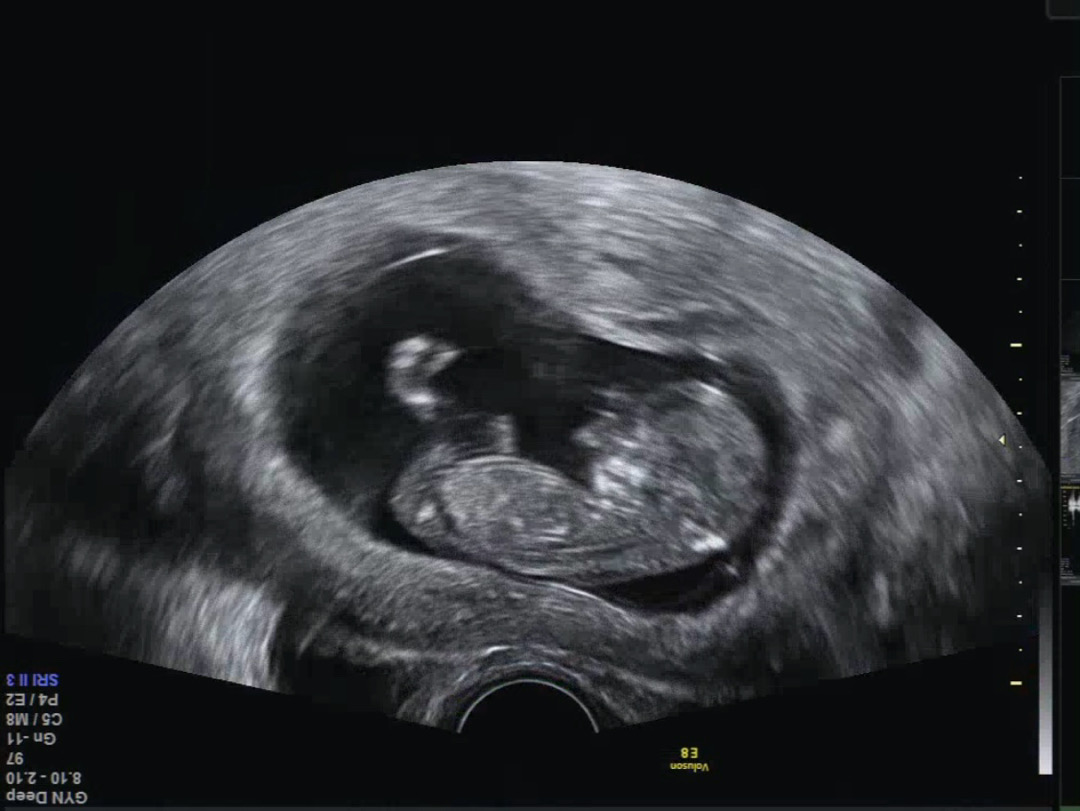

한번 봐주세용 11주 4일❤️

아직 이르긴하지만 성별이 너무 궁금해용 아들일까요 딸일까요🤭